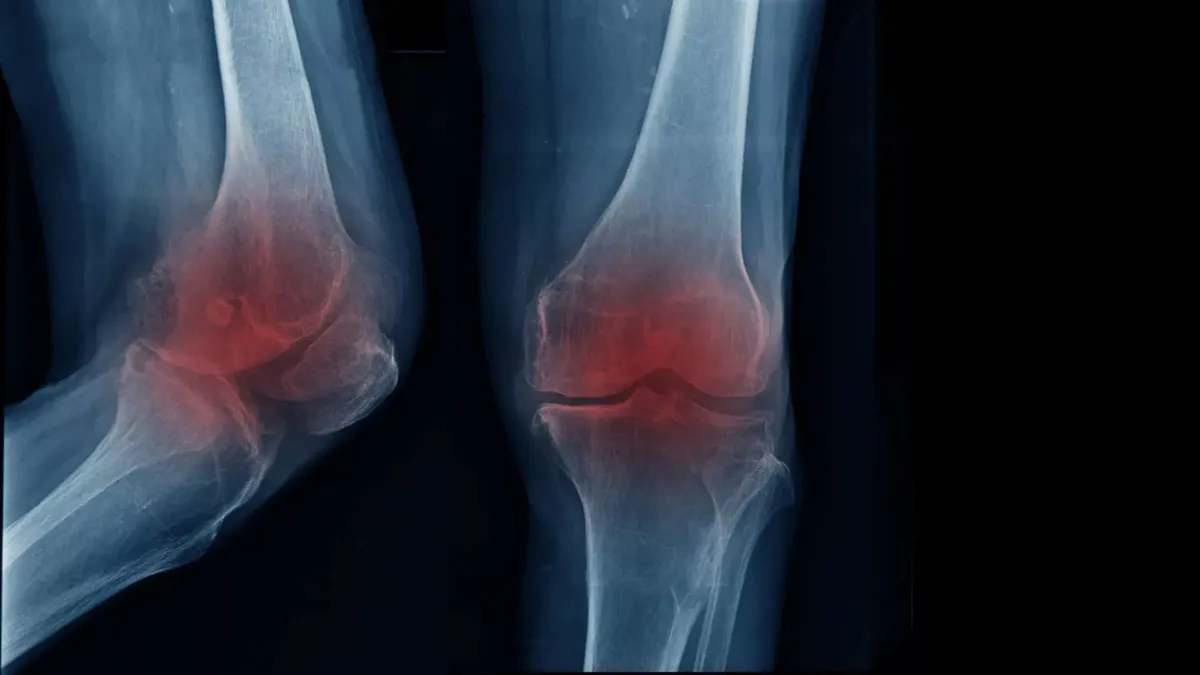

چطور آرتروز زانو با تقویت توده عضلانی قابل درمان است

تحقیقات جدید نشان داده که می‌توان با تقویت عضلات ساق پا، از شدت بیماری آرتروز زانو کاست یا احتمالاً آن را از بین ببرید.